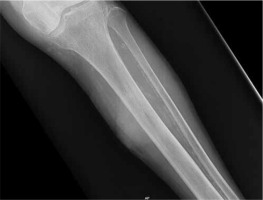

We report a case of a 78-year-old female patient with medical history of hypertension and benign tumour of the uterus for which she had undergone hysterectomy 12 years earlier. She presented at our emergency department due to an atraumatic pretibial swelling of the left leg that she noticed 1 month earlier. Plain radiography did not detect any pathology, although decreased soft tissue transparency around the proximal tibia was seen (Figure 1). Under local anaesthesia the swelling was incised and a serous-bloody collection evacuated. During the procedure the tibial bone surface was found to be irregular, but no further investigations were made, and the patient was discharged. The wound dressing was changed every 2 days in the outpatient service. Swab culture from the incised place was sterile.

Figure 1

Plain radiography reveals altered bone structure of the proximal tibial diaphysis as well as decreased surrounding soft tissue transparency